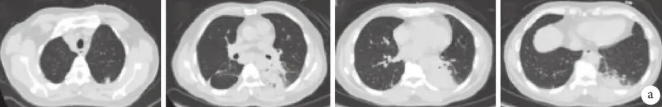

抗感染治疗3天后患者症状无明显好转,仍有发热。为了进一步明确病原学诊断,行支气管镜下取支气管肺泡灌洗液(bronchoalveolar lavage fluid,BALF)和肺组织。BALF宏基因组二代测序(metagenomics next-generation sequencing,mNGS)检测示马尔尼菲篮状菌(序列数3 067),BALF培养可见TM(1×104)生长。肺组织病理示肺泡腔内可见组织细胞及纤维素,间隔淋巴细胞浸润,局灶可见少许纤毛柱状上皮、纤维素及中性粒细胞渗出物;特殊染色GMS(–),PAS(–),抗酸(–),革兰(–),抗酸荧光(–),真菌荧光(–);肺组织改变为肺炎症性病变,考虑为感染,未见特殊病原菌(图3a)。追问病史:患者近期有广西旅游史,但无明确竹鼠的接触史。

图3 支气管镜肺组织活检病理像(×100)

a. 首次病理结果

患者再次发热,白细胞升高,左下肺病灶在规范抗真菌(伏立康唑浓度达标)治疗后先缩小后增大,而全身PET-CT 提示TM感染的治疗有效,未见肿瘤征象。为了进一步明确病灶再次增大的病因,再次行支气管镜检查,左下肺病灶位置取BALF和组织活检。BALF的mNGS的结果提示:嗜肺军团菌(序列数67108)。呼吸道病原体核酸检测:嗜肺军团菌(+)。肺组织病理(左下叶背段送检肺组织)):肺泡腔见渗出的纤维素及机化灶,间隔少量中性粒细胞及淋巴细胞浸润,特殊染色结果GMS(–),抗酸(–),抗酸荧光(–),真菌荧光(–),符合纤维素性机化性肺炎(图3b)。考虑诊断嗜肺军团菌肺炎,遂加用左氧氟沙星注射液抗军团菌治疗,继续维持伏立康唑的治疗。患者体温逐步下降,症状较前明显好转。该患者出现病情的反复,多次出现胞内菌(TM、嗜肺军团菌),但无常见的可导致免疫缺陷的基础病。完善相关检查:TBNK细胞亚群提示CD4+ T细胞、CD8+ T细胞,B细胞,NKT细胞等数量未见异常;免疫八项未见明显异常;随后查抗IFN-γ自身抗体提示阳性,滴度1∶1600。同时,分离患者血清中抗IFN-γ自身抗体进行中和实验,提示对IFN-γ具有较强的中和活性。

b. 再次发热后第二次病理结果。